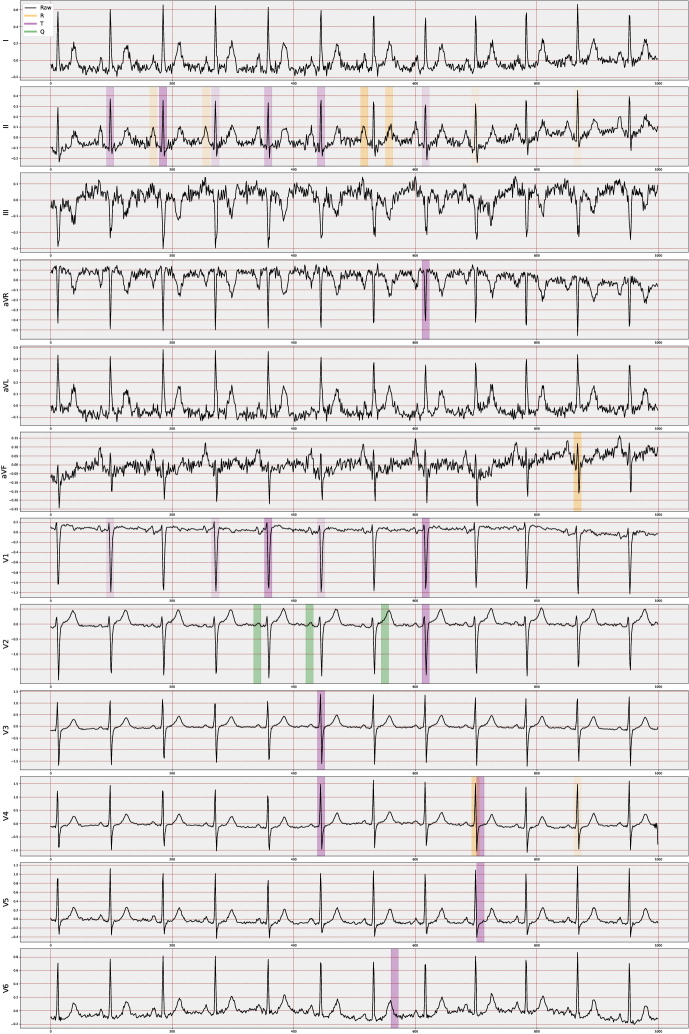

In this section, we present the details of the system we propose. The methods in the system involve several main steps: preprocessing the data, extracting and selecting important ECG signal features, gathering clues, generating reports and producing visualizations (Figure 1).

4.3 VCCE: Visualizing Counterfactual Clues on Electrocardiograms

We have developed a visualization method, VCCE, to enhance the presentation stage of the obtained counterfactual clues to the end-user, i.e., the clinician. This structure involves highlighting counterfactual clues obtained from the patient’s signal in the ECG report. For visualization, we offer various options that allow the display of peaks in chosen regions along with advanced features. These features are computed via amplitude differences and are presented as lines with their distance values overlaid on the ECG signal. Moreover, when visualizing counterfactuals, the more a specific feature is selected in an alternative world, the more it is strongly highlighted on the ECG report.

In essence, this approach, may adaptable independently of the ECG task, enables us to observe changes in PQRST across many “possible worlds," providing a means to perceive alterations across different scenarios. The main justification for assuming the applicability of VCCE across a wide range of ECG tasks is fundamentally rooted in the nature of the employed ECG features, similar to other ECG-dependent cardiac conditions. These features are extracted based on the structure of the P-, Q-, R-, S-, and T-waveforms (cardiac cycle) at a beat level, which remains a consistent term across all ECGs. The key advantage lies in the fact that these derived features offer distinct temporal and amplitude-level information that is inherently interpretable. Consequently, we can not only numerically analyze the generated counterfactual scenarios but also precisely determine their impact on specific waves within particular leads and beats.

In the proposed study, we note that the selected top 20 features are predominantly non-temporal due to their dependence on lead-wise amplitude characteristics across all MI cases in the dataset, with RR_Next being the only temporal one. Therefore, our visualization method primarily focuses on amplitude-based (non-temporal) features. Additionally, we have included four more features, selected by domain experts, to enhance individual resolution, such as distinguishing between inferior and anterior case differences. Consequently, we initiate a decoding process to unfold the temporally compressed beats. This decoding involves expanding the feature names to indicate the specific area influenced by the counterfactuals responsible for the change, encompassing details such as the lead, the waveform feature, and the beat associated with the counterfactual’s impact. This way, we are individually marking the features that contribute the most significant distinction between the two diagnoses.

5.3 Visualization of Counterfactual Clues

Understanding changes solely based on ECG features remains a time-consuming process within generated scenarios. Integrating simplified visualizations could effectively improve the grasp of pertinent indicators. To evaluate both the generated clues and the complete ECG report, we adopted custom measurement techniques. These measures involved assessments by expert cardiologists, incorporating both blind evaluations and interactive appraisals. This strategy improved the comprehensive evaluation of the generated clues.

In addition to the analysis in Section 5.2, our preliminary empirical investigations on visual assessments have led domain experts to conclude that the incorporation of four additional features (V2_T, V3_T, V4_T, and V6_T) can be both beneficial and necessary. These features have not only enhanced the quality of visualization but also improved the classification accuracy. This was evident in the identification of local MI cases, such as case ID 3234.0 in the dataset, where the system accurately identified 6 out of 7 individual beats, compared to the previous 2 out of 7.